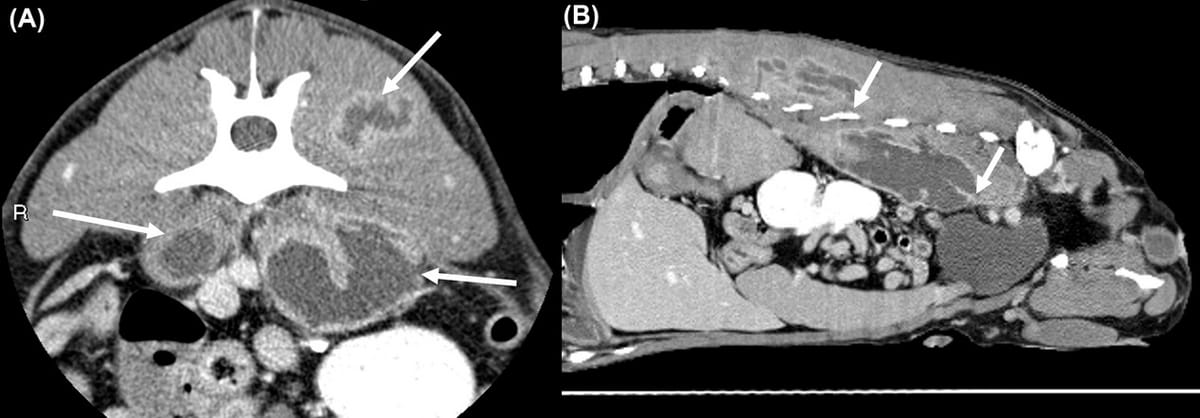

Postcontrast parasagittal and transverse (at L3-4) CT from a dog with bilateral hypaxial and left epaxial lesions showing severe enlargement of the left hypaxial muscles with central fluid attenuation (HU 22) and peripheral contrast enhancement. Soft tissue window level: 35 and window width: 300

Results: Twelve dogs met the inclusion criteria. CT findings of hypaxial muscle lesions caused by migrating vegetal foreign material included hypaxial muscle enlargement, abscesses with central fluid attenuation and irregular contrast enhancing rim, periosteal reaction and lysis of adjacent vertebrae, and retroperitoneal effusion. Radiography and ultrasound imaging were used as adjunct modalities for diagnosis and were beneficial in identifying some of the lesions.

Conclusion: The CT features of hypaxial muscle abscesses in this sample of 12 dogs included unilateral or bilateral heterogenous hypaxial muscle enlargement, central fluid attenuation with rim enhancement of the hypaxial muscles, and lumbar vertebral osteomyelitis characterized by lumbar vertebral lysis and periosteal reaction. Findings supported including vegetal foreign material in the hypaxial muscles for dogs with these CT features and recommending further investigation through the use of ultrasound and/or exploratory surgery.